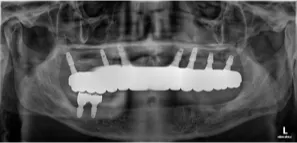

풀아치 임플란트 수술후 (2024.02.29)